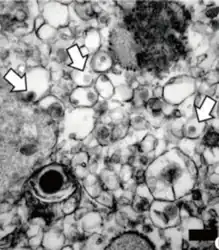

- Transmission electron microscopy image of Vero cells infected with Zika virus

A longitudinal study shows that 6 hours after cells are infected with Zika virus, the vacuoles and mitochondria in the cells begin to swell. This swelling becomes so severe, it results in cell death, also known as paraptosis. This form of programmed cell death requires gene expression. IFITM3 is a trans-membrane protein in a cell that is able to protect it from viral infection by blocking virus attachment. Cells are most susceptible to Zika infection when levels of IFITM3 are low. Once the cell has been infected, the virus restructures the endoplasmic reticulum, forming the large vacuoles, resulting in cell death.[30]